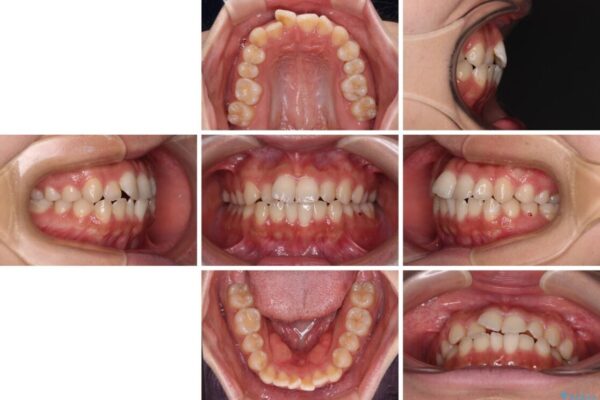

前歯のデコボコを気にして来院された患者様です。

マウスピース矯正のような自己管理の煩わしさは避け、早く治療を終えたいとのことで、ワイヤー装置による矯正治療を行うこととしました。

当初予定通り、1年で治療を終えることができました。

治療前

• 【モニター】短期間で終わりたい ワイヤー装置での非抜歯矯正 治療前画像